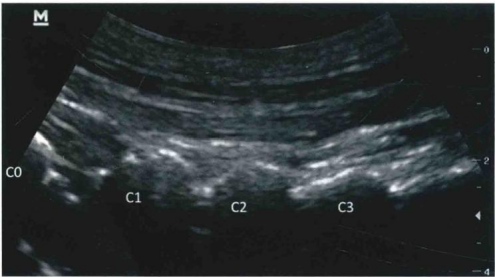

超声引导下穿刺分为外侧入路和后侧入路

采用平面内技术,在选定的穿刺点,以长3.5英寸带芯穿刺针在超声探头的下方以小关节为靶点从尾侧向头端方向进针( 图9和图10 )。

图9 / 超声引导下颈椎小关节内阻滞